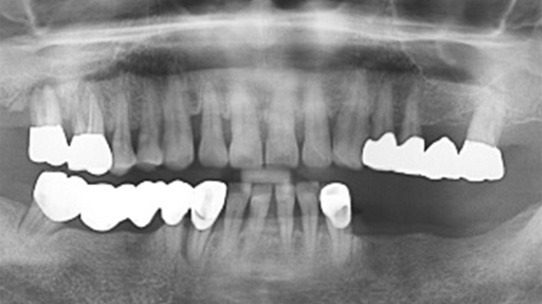

잇몸뼈가 녹아내려 다른 병원에서 임플란트 12개 진단을 받고 내원, 고운미소에서 치주치료를 시행한 결과 전치부 잇몸이 개선되어 발치 하지 않고 크라운으로 수복하였고, 어금니에 6개의 임플란트를 식립하였습니다.

잇몸 염증으로 치조골 손실이 많은 상태

잇몸건강이 회복된 앞니는 크라운으로 수복